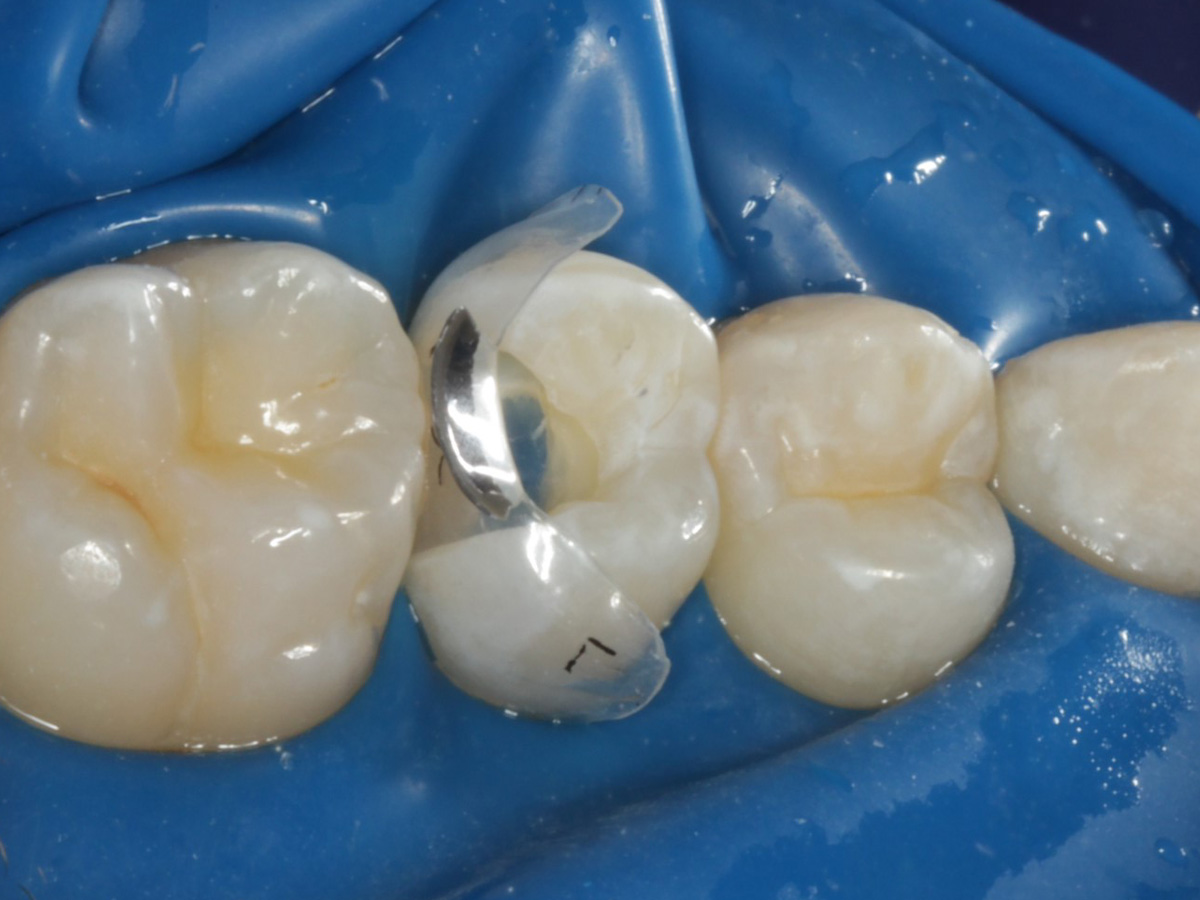

Abbildung 16

Nach Anbringung des Bioclear Twin Ring Universal und Lichthärtung des Einkomponentenadhäsivs